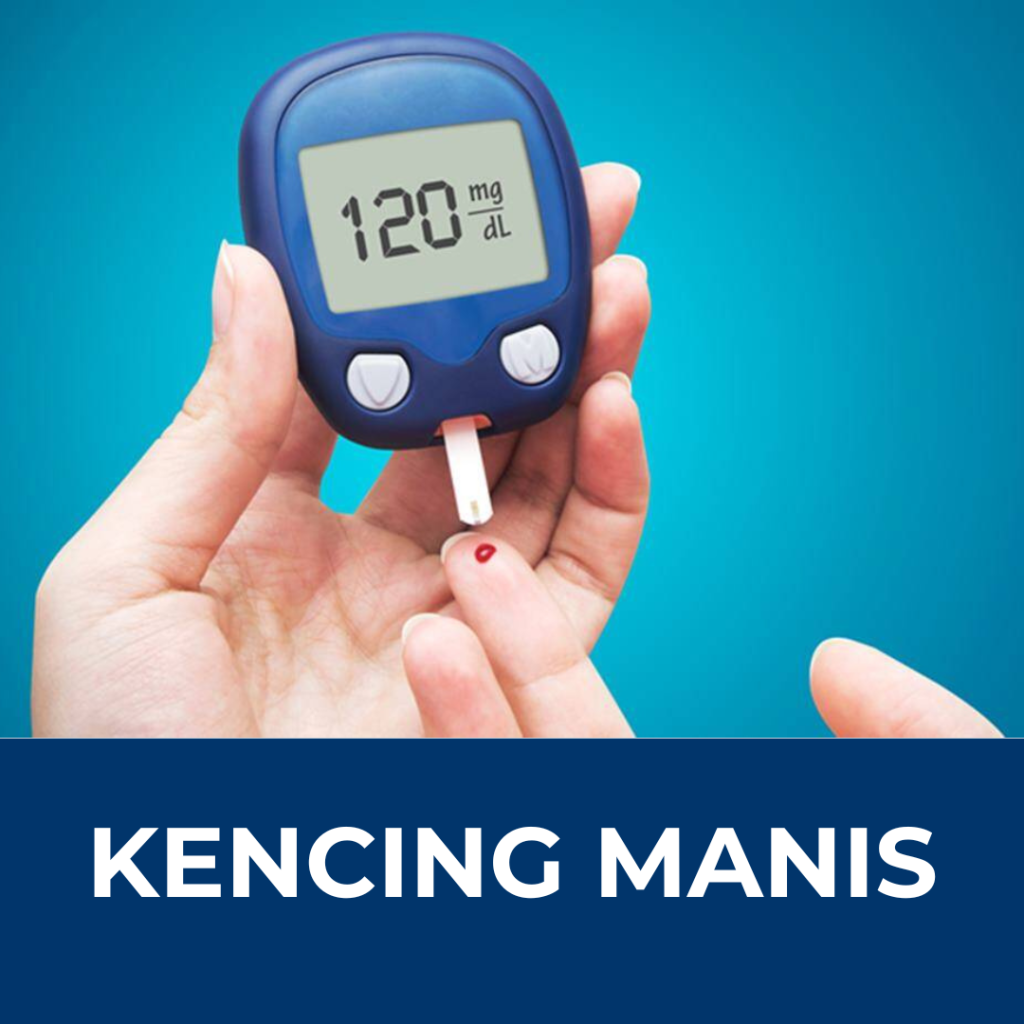

Ramai yang mati mengejut akibat strok dan serangan jantung. 75% Rakyat Malaysia Menghidap Kencing Manis dan Kolesterol Yang Tinggi.

Kerap Kencing

Jika anda mempunya Salah satu tanda atau simptom masalah dibawah, maka tolong baca sampai habis!

Jangan Biarkan Masalah Ini Berterusan!

Solusi Terbaru Hasil Kajian Selama 45 Tahun oleh Professor Shoji Ohga Berjaya Temui Cara Mudah Turunkan Bacaan Kencing Manis dan rawat Tiga Serangkai

- Merawat Kencing Manis

- Menurunkan Kolesterol

- Menstabilkan Tekanan Darah

Penghidap masalah kencing manis, tekanan darah tinggi, kolestrol dan sakit jantung sesuai ke?

Sangat sesuai dan kandungan bahannya adalah kategori makanan tambahan, bukan ubat. Berasakan 100% bahan semulajadi. Sangat disarakankan untuk mengamalnya setiap hari